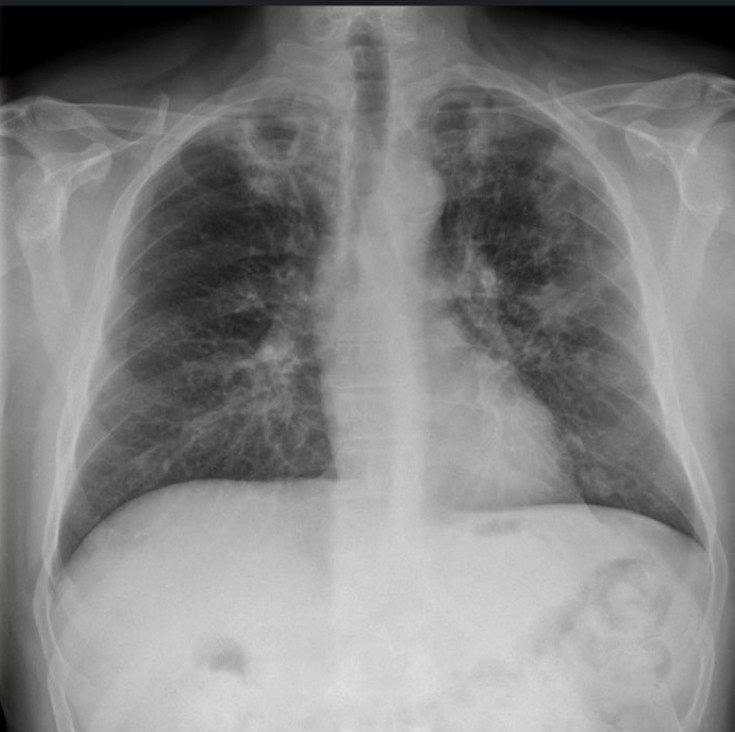

Pneumonia

A 30-year-old homeless male presents to your tertiary ED with a productive cough, fever, shortness of breath and haemoptysis. He …

HIV with fever, cough and confusion

A 45-year-old man known to be HIV positive, presents to your department with fever, nonproductive cough, weight loss and mild …

Active pulmonary tuberculosis

A 45-year-old Nepalese man presents to your Emergency Department with a 2-week history of cough, fever, haemoptysis and weight loss …